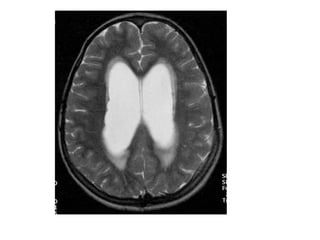

IRM:

 Dilatation ventriculaire: Hypersignal péri-

ventriculaire (résorption)..

 Intérêt pour la fosse postérieure, et les coupes

sagittales.

 Possibilté d’image cinétique (de “flux”).

IRM:  Dilatation ventriculaire:Hypersignal péri- ventriculaire (résorption)..  Intérêt pour la fosse postérieure, et les coupes sagittales.  Possibilté d’image cinétique (de “flux”).